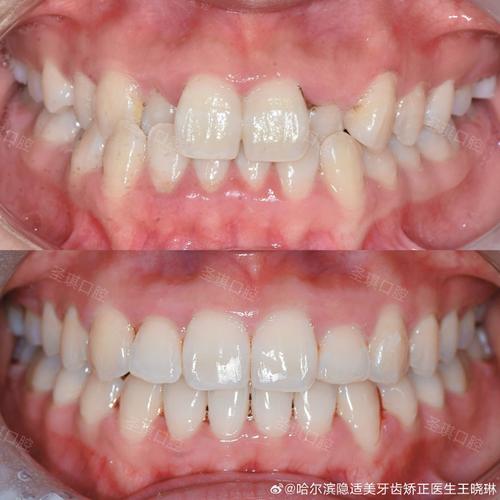

(图片来源网络,侵删) -

(图片来源网络,侵删)